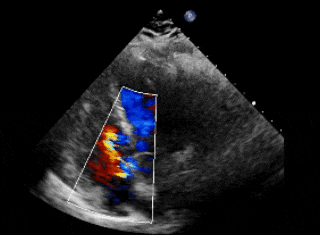

术前超声、造影

超声下可见右冠窦与右心房相通,主动脉短轴切面示类似膜周部室缺

主动脉瓣上造影,破口约5mm